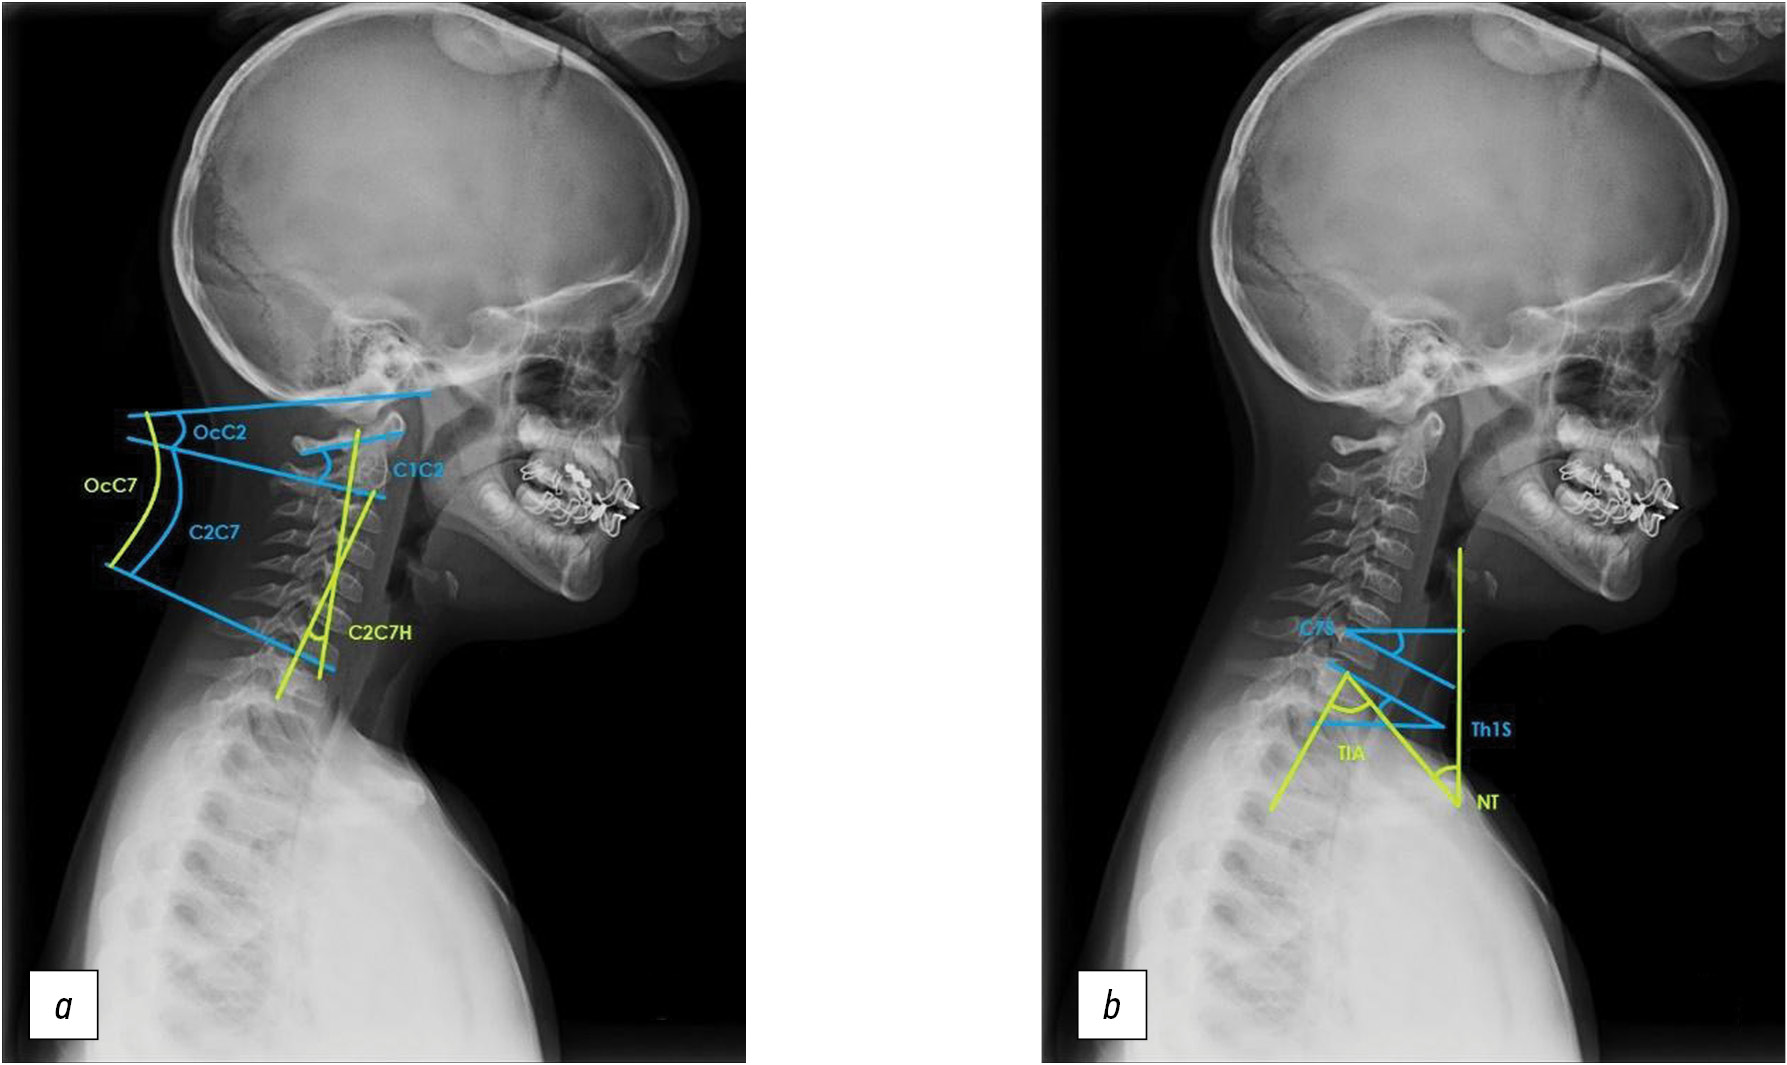

Assessment of target indicators

Based on X-ray data, the angular parameters of the cervical sagittal balance, most frequently mentioned in the literature, assessed by the Cobb method (Oc–C2, Oc–C7, C1–C2, C2–C7, C2–C7H, C7S, Th1S, TIA, and NT), were calculated [3, 5]. The method of calculating these parameters is presented in Fig. 1.

Fig. 1. a, b — technique for measuring cervical sagittal balance parameters.